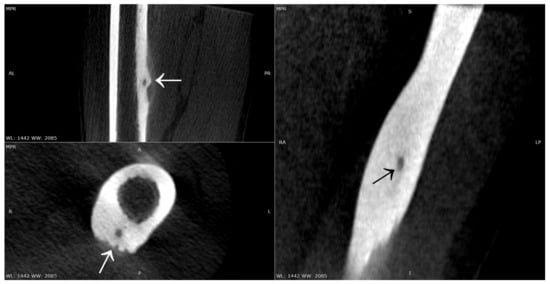

2. Materials and Methods